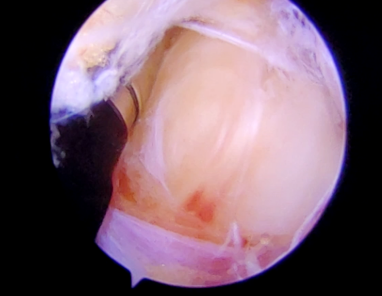

镜下显露肿物

潘海乐教授带领团队手术如期进行,术中,关节镜处理关节内损伤后发现肿物并未在关节内出现隆起等间接征象,突破关节囊探查肿物难以获得满意视野,盲目操作和应用射频离子刀止血极易出现腋神经及重要血管损伤,而即使少量出血也会严重影响镜下视野,手术将难以完成。在此情况下,潘海乐教授决定邀请术中超声引导,在超声医学科吴涵副主任医师的操作下,肿物被迅速定位,并确定了神经及动脉位置。在超声引导下,潘海乐教授以钝性交换棒避开神经血管穿至肿物旁,直至触及肿物,通过交换棒导入关节镜,人为建立腔隙充入灌注液,建立观察入路视野内见肿物边界清晰,紧邻腋神经,并有局部与腋神经及周围组织粘连,同时镜下可见腋动脉搏动,超声引导下建立操作入路,精细分离肿物与周围组织,剥离肿物与腋神经的粘连,终于在刨刀、离子刀、交换棒等工具多次从腋神经及腋动静脉等结构周围穿梭后,肿物被完整剥离并摘除。术后患者既往的不适感消失,术后病理为梭形细胞肿瘤。